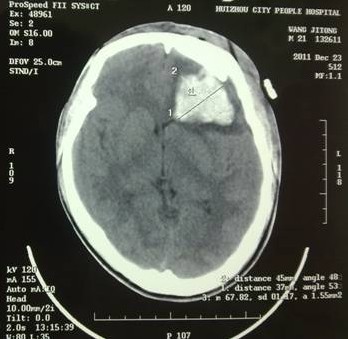

于是家屬慕名求助于我院余永強(qiáng)主任,在傷后第三天轉(zhuǎn)來我院。余永強(qiáng)主任主持術(shù)前討論,決定為患者施行微創(chuàng)手術(shù)清除血腫。通過CT掃描進(jìn)行術(shù)前精確定位,隨后在局麻下進(jìn)行微創(chuàng)手術(shù)。術(shù)中利用余主任設(shè)計(jì)研制的“e形微創(chuàng)手術(shù)定向儀”作引導(dǎo),將穿刺針準(zhǔn)確無誤置入血腫靶心,順利地清除了絕大部分血腫。術(shù)后復(fù)查頭顱CT,血腫清除超過90%(圖2)。憑借微創(chuàng)技術(shù),頭皮僅僅只需要一個(gè)直徑3毫米的小孔,通過一根高科技微創(chuàng)穿刺針,便可達(dá)到同樣的甚至更好的治療效果(圖3)。術(shù)后留置引流1天,第7天即痊愈出院。手術(shù)達(dá)到近乎“完美”的效果!患者親屬大為感慨微創(chuàng)手術(shù)的“神奇”,術(shù)后專程送來錦旗一幅――“微創(chuàng)手術(shù)顯神功” ?。▓D4)

圖2(2):術(shù)后2周復(fù)查,腦組織恢復(fù)良好。